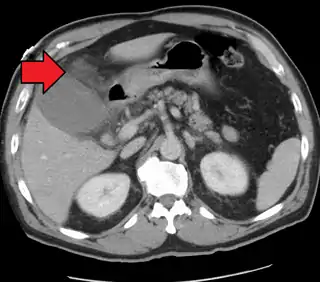

![]() Colecistitis aguda como se ve en la TC.Obsérvese la acumulación de grasa alrededor de la vesícula biliar agrandada. | ||